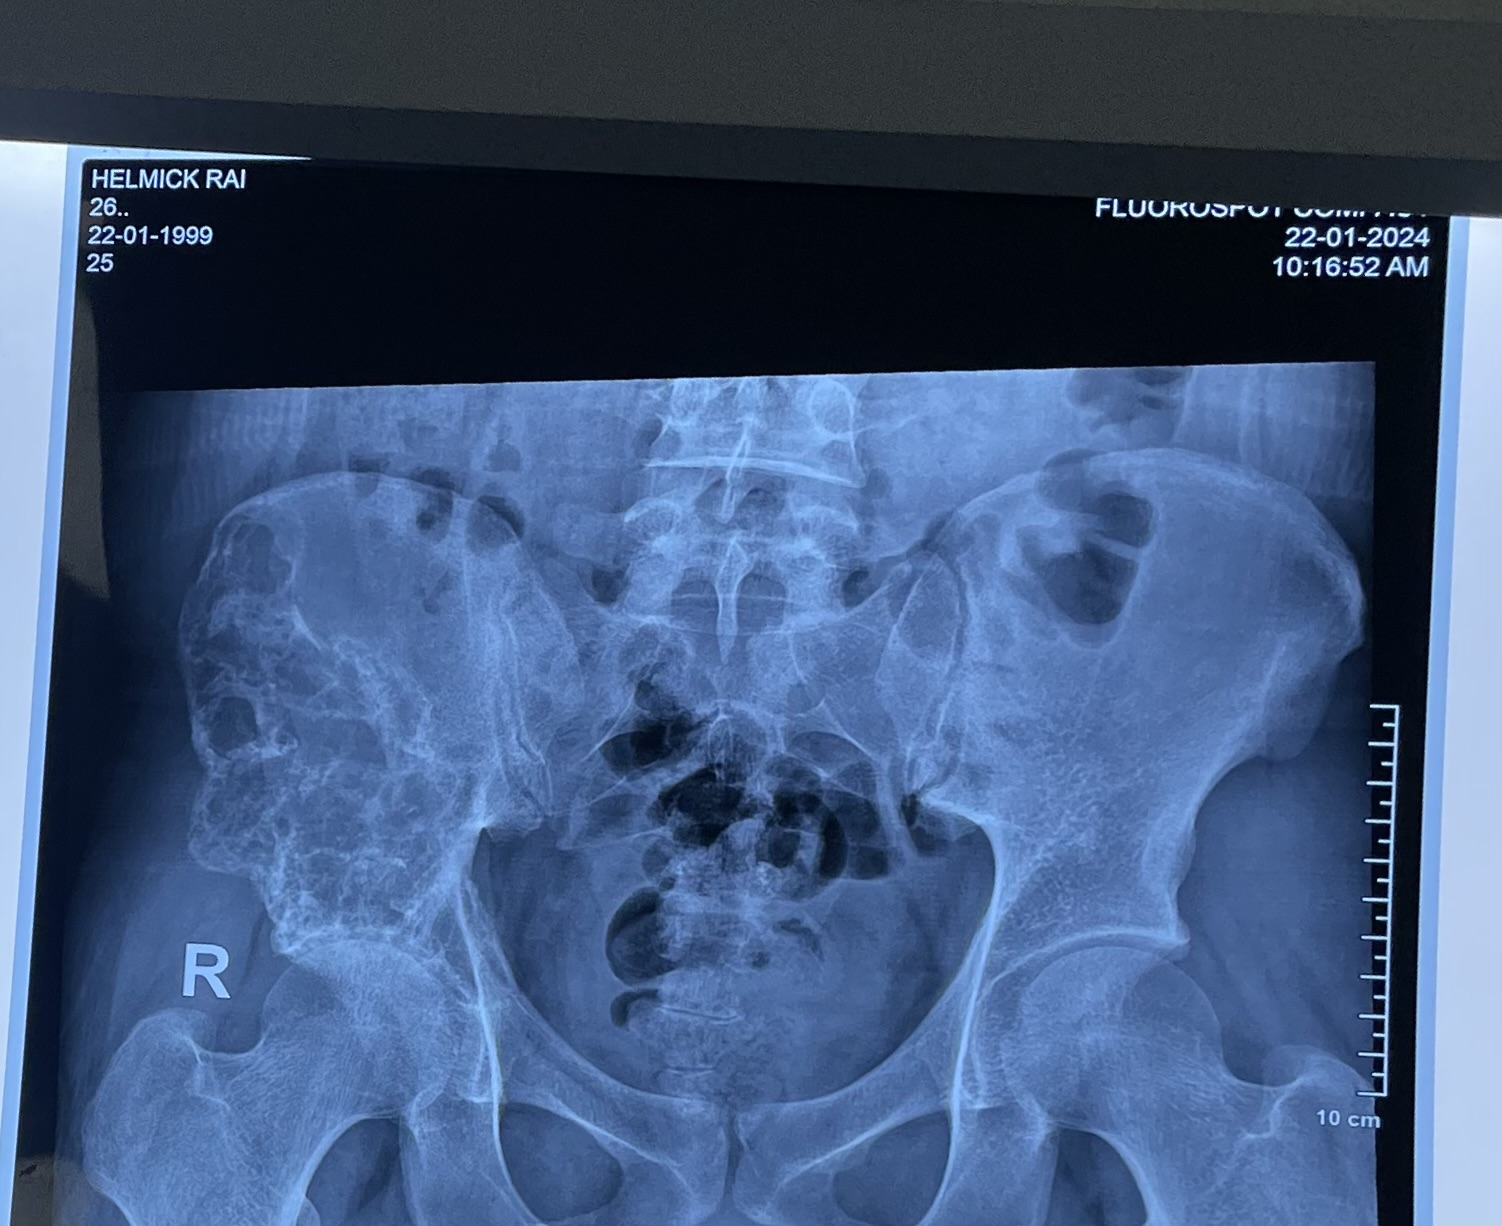

I have cancer on pelvis bone help ((

I dont have money for treatment and its very costly for treatment i need help please im from a poor country and dont have enough donation